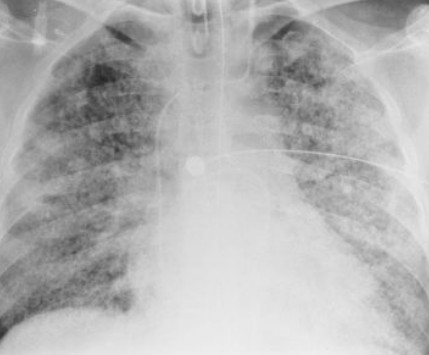

RA: covid-19

multiple bilateral patchy consolidations or opacities